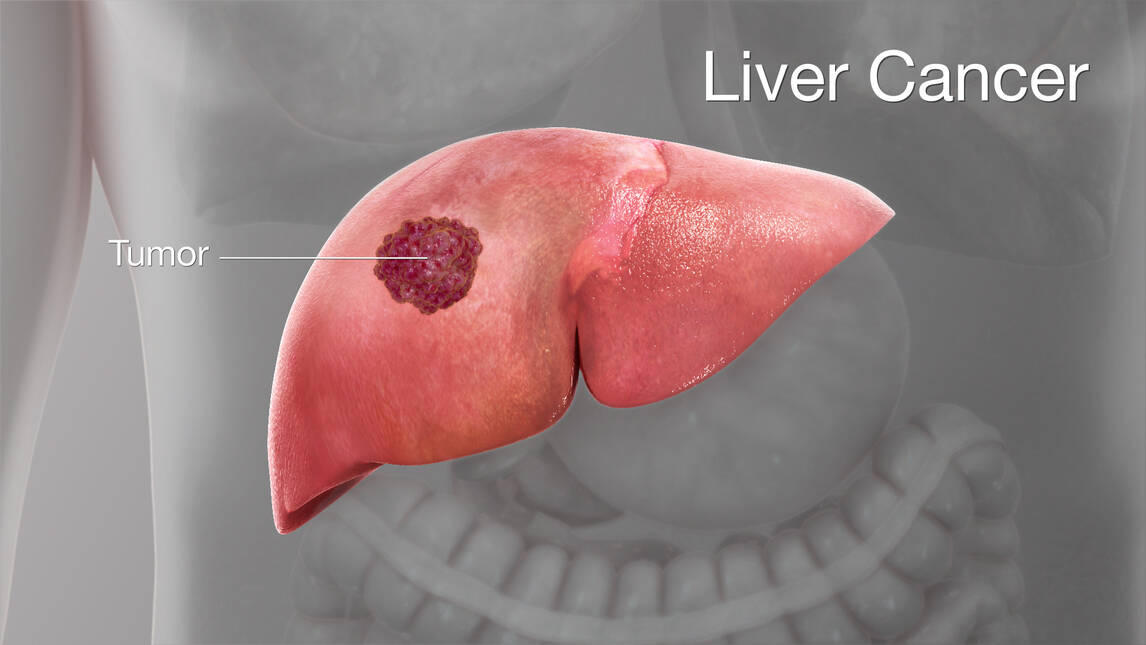

Liver cancer, specifically primary liver cancer, refers to a harmful tumor that originates in the liver. It can be classified into various types, with hepatocellular carcinoma (HCC), also known as hepatoma, being the most prevalent. This particular type of primary liver cancer initiates from the principal cell type found in the liver – the hepatocytes.